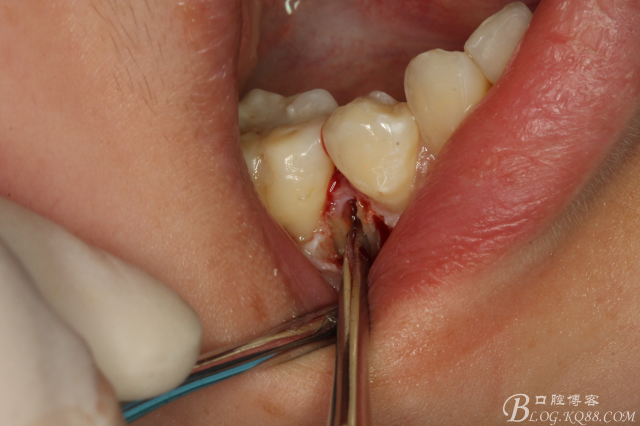

圖15.挺松的45牙根,牙根已脫位至創(chuàng)口邊緣。

圖16.取出45牙根,牙槽窩完整、不變形。

圖17.清理牙槽窩,切口止于膜齦聯(lián)合處,這樣術(shù)后不腫脹。

圖18.放膠質(zhì)銀

圖19.縫合

圖20.拔除的45牙根。